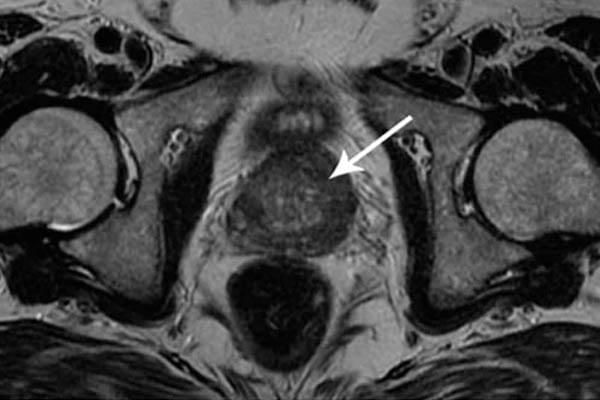

Saya ingin menunjukkan beberapa foto tentang apa yang terjadi pada sistem genitourinari dan organ dalam lainnya dari seorang pria ketika dia berhenti berhubungan seks.

alt_text

Seperti inilah peradangan prostat karena stagnasi di dalamnya (dengan tidak adanya pengosongan testis, yang terjadi saat berhubungan seks). Peradangan yang berkepanjangan pertama-tama mengarah ke adenoma, dan kemudian ke kanker prostat (dari mana, menurut statistik, 38% pria meninggal). Dengan tidak adanya seks, ini selalu terjadi, itulah sebabnya adenoma dianggap sebagai penyakit orang tua.